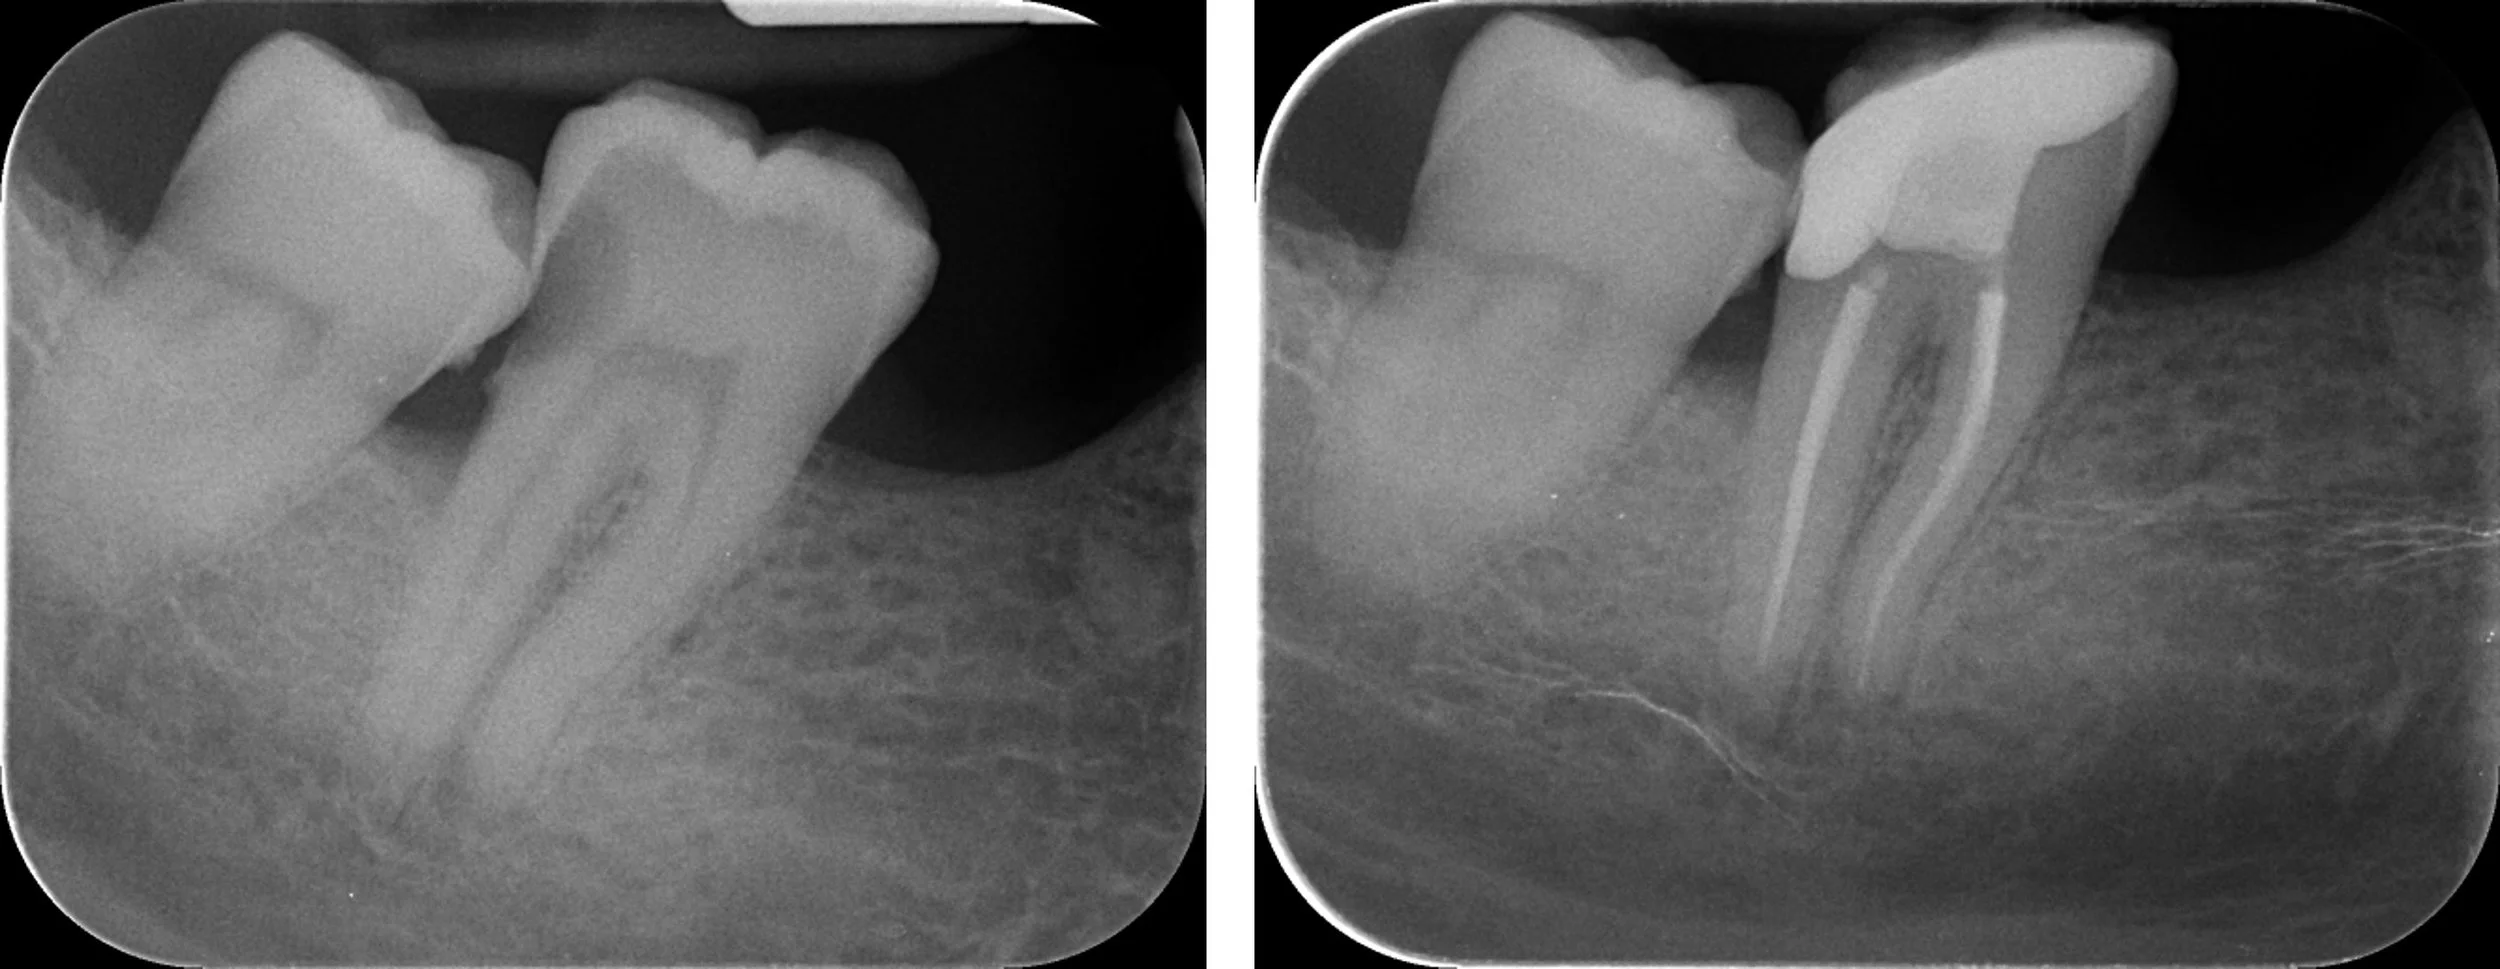

Root canal treatment radiograph